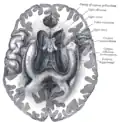

![]() Base of brain (Tuber cinereum visible at center). | |

The tuber cinereum is the portion of hypothalamus forming the floor of the third ventricle situated between the optic chiasm, and the mammillary bodies.[1][2] The tuberal region is one of the three regions of the hypothalamus, the other two being the chiasmatic region and the mamillary region.[1]

The tuber cinereum is situated caudal to the optic chiasm, medial to the optic tract (which flanks it on either side), and rostral to the two mammillary bodies.[4] is continuous anteriorly with the lamina terminalis, and laterally with the anterior perforated substances.